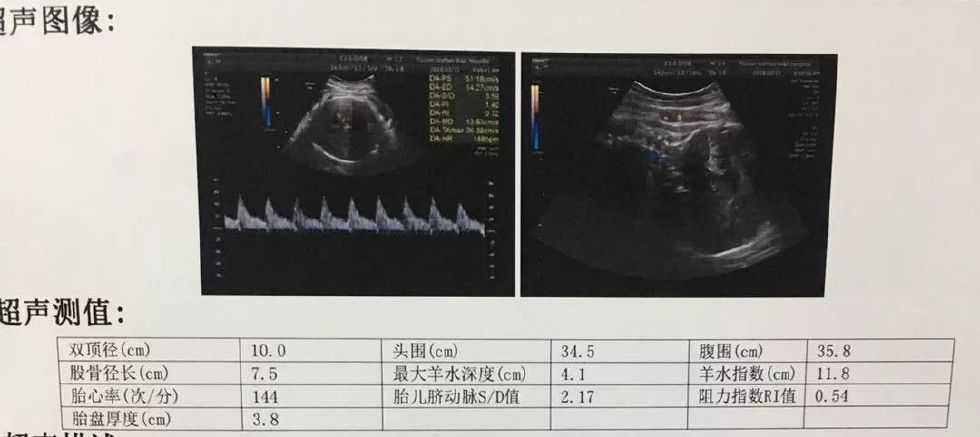

一直到了39周+4天,眼看预产期就要到了,做最后一次产前B超。

产科主任一看,说:“哎哟,这双顶径10了,没几个宝宝头能那么大的。你肚子不大,看不出是要临产了,可见小家伙个头很实在啊,预计有七斤半左右。你确定还要坚持顺产吗?”

听到这些话,我直接就懵逼了——什么?七斤半?上次37周B超说才六斤多,怎么这两周饭量小了,天天暴走,怎么还能长那么快!?